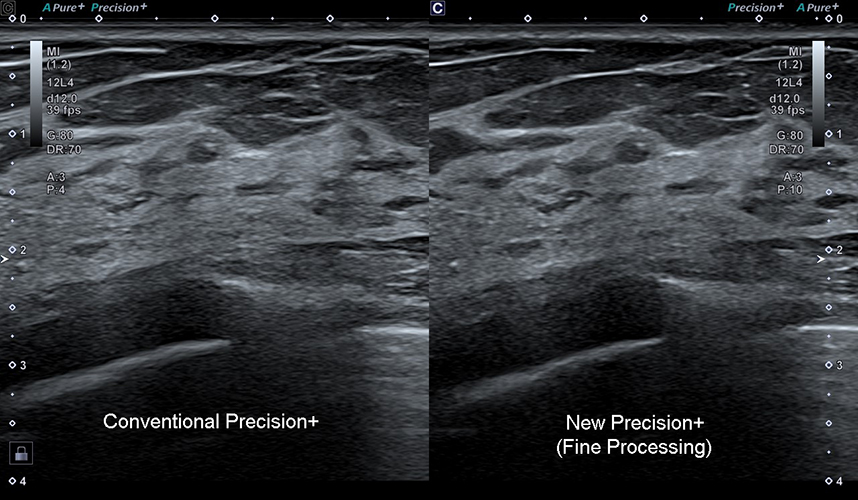

Precision+ Режим точної обробки

Precision+ відомий своєю видатною продуктивністю у створенні однорідних зображень із чіткими контурами, покращеною рівномірністю зображення та зменшенням артефактів. Новий режим Fine Processing Aplio beyond забезпечує ще чистіші зображення з більш чіткими контурами.